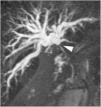

A 51-year-old man was evaluated for obstructive jaundice associated with mild dyspepsia. He had an unremarkable past medical history and physical examination revealed no significant findings except for jaundice. Laboratory test results showed altered liver enzymes (total bilirubin 20.1mg/dl, direct bilirubin 18.8mg/dl, AST 53U/l, ALT 144 U/l, GGT 386 U/l, ALP 203 U/l). A computed tomography (CT) scan and subsequent magnetic resonance cholangiopancreatography (MRCP) demonstrated a 1.2cm hilar mass, which constituted hilar stricture and occlusion of the biliary tract and its dilation in the intrahepatic area (fig. 1), suggesting hilar cholangiocarcinoma (Bismuth-Corlette II). Percutaneous cholangiography for internal-external biliary drainage confirmed the hilar stricture (fig. 2A); cholangiography performed 10 days later showed its normalization (fig. 2B). The patient underwent cholangioscopy that confirmed a normal biliary duct at the hilum (fig. 3) and endobiliary forceps biopsies were taken in the same session. The histopathologic evaluation revealed transmural chronic inflammatory cell infiltrates, with no signs of malignancy. Immunohistochemical staining showed IgG4-positive plasma cells (figs. 4 A and B). MRCP at 6 months confirmed a normal biliary tree (fig. 5).